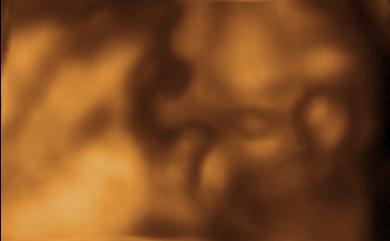

Our 3 D photos as the baby looks away, hides her face, etc. We finally got a photo where the umbilical cord isn't right in her face, and she put her arms up!...

See... she's looking right out at you! Nifty, huh?